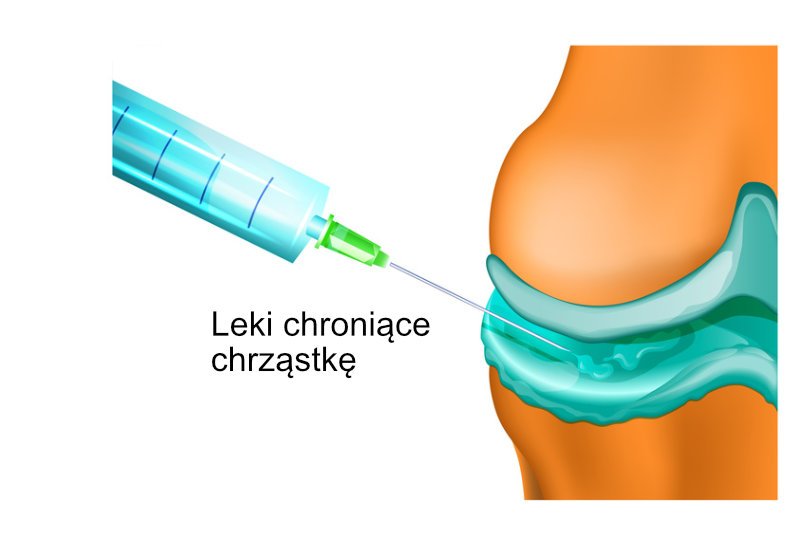

Nieoperacyjne leczenie stawu kolanowego (zastrzyki dostawowe)

Najskuteczniejszą drogą podania leku jest jego bezpośrednie wstrzyknięcie do stawu. Dzięki temu 100% podanego leku dociera tam, gdzie powinno. Podczas wykonywania zastrzyku można dodatkowo usunąć ze stawu zapalny płyn. Odpowiednie znieczulenie i specjalna technika podania sprawiają, że bolesność takich zabiegów jest minimalna. Zastosowanie monitorowania za pomocą fluoroskopii daje pewność, że lek zostaje precyzyjnie podany nie tylko do wnętrza stawu, ale dokładnie pomiędzy uszkodzone chrząstki.

W zależności od stanu pacjenta do stawu kolanowego podaje się leki ochraniające chrząstkę (wiskosuplementacja), hamujące zapalenie oraz stymulujące regenerację stawu. Zastrzyki uśmierzają ból, hamują postęp choroby i zmniejszają sztywność.